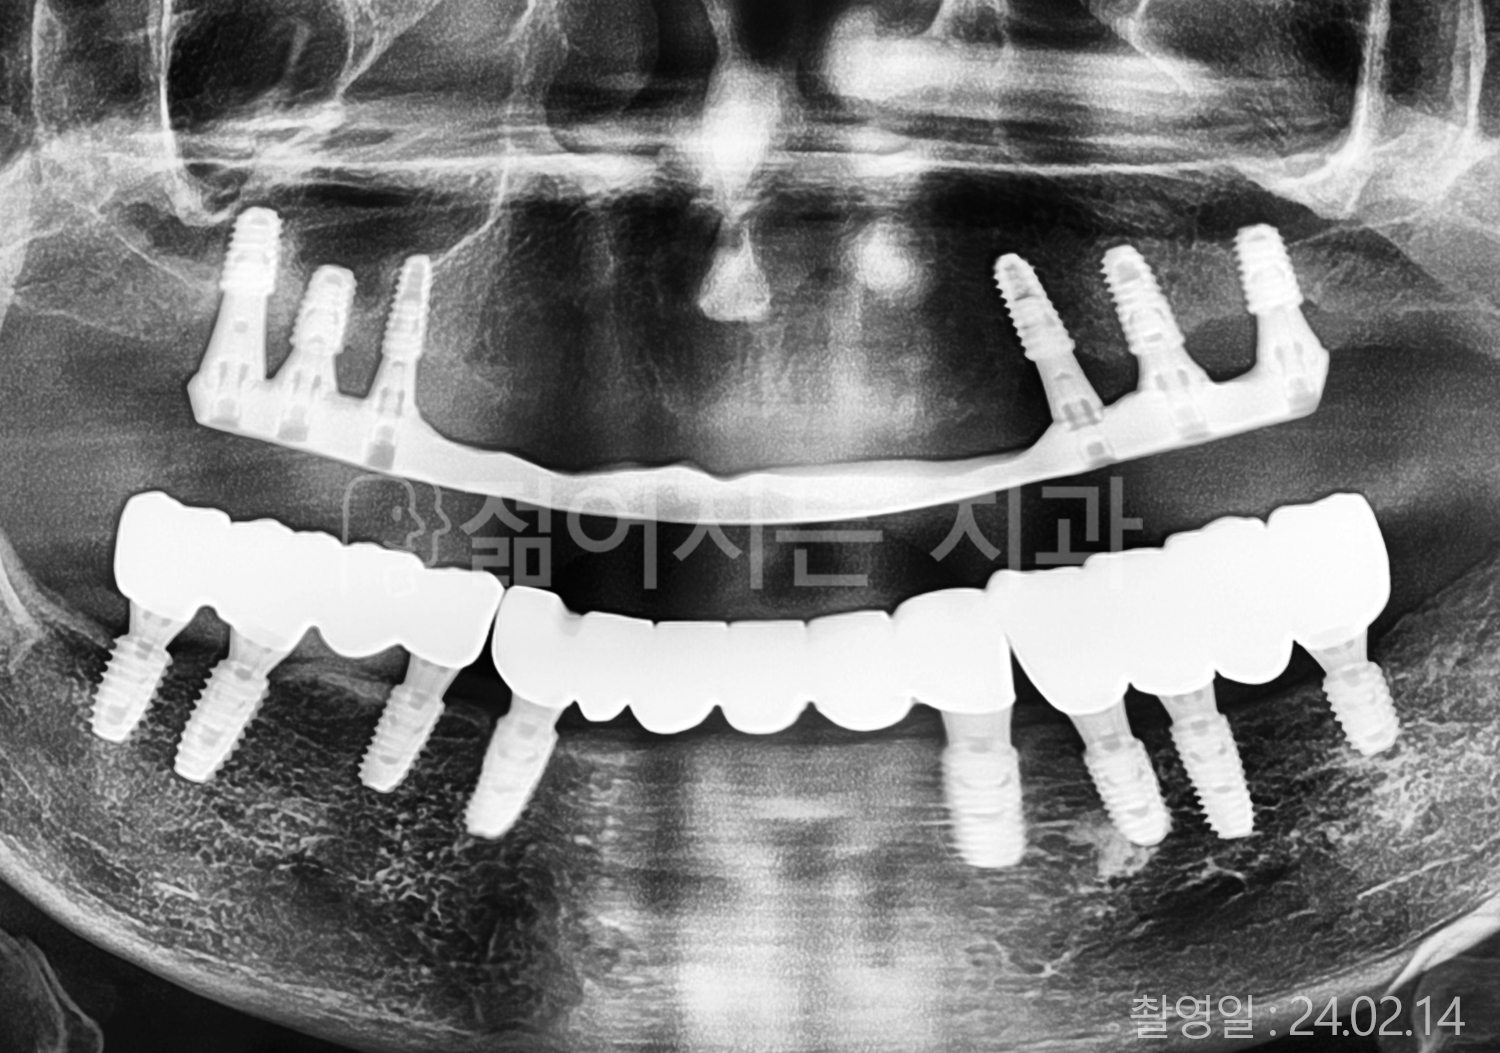

• 50대 고혈압, 당뇨, 고지혈증 전체치아 10개 이상 임플란트

• 60대 골다골증, 간경화 전체치아 10개 이상 임플란트

• 60대 고혈압, 고지혈증 전체치아 10개 이상 임플란트

• 50대 고혈압, 당뇨 전체치아 10개 이상 임플란트

• 60대 고혈압 전체치아 10개 이상 임플란트